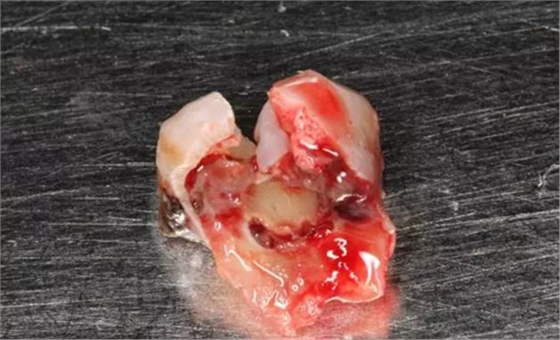

圖7. 37牙冠碎裂。多生牙壓迫吸收程度嚴(yán)重。

圖8.拔除的37頰側(cè)的牙根完全被壓迫吸收完。